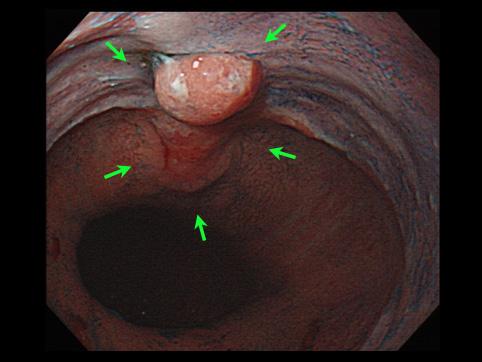

疾病(病理主体)的分类恶性上皮性肿瘤/腺癌

部位(按器官分)2个以上的内脏器官/

检查方法内窥镜

肿瘤的肉眼分类0型(表在型)/IIc型(IIc+IIa)

肿瘤最大直径25~29

肿瘤的深度sm